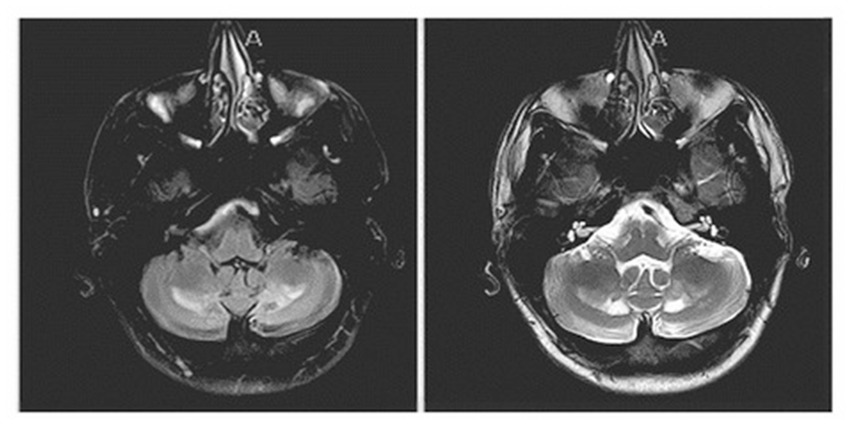

On evaluation, his unified Parkinson’s disease rating scale (UPDRS) part 3 OFF score was 37/108 and ON score was 31/108. Additionally, the tremor rating scale (Fahn–Tolosa–Marin) pre-DBS total score was 32/144 (moderate functional disability). On examination he exhibited left predominant rest tremor, rigidity, bradykinesia, gait changes without postural instability with additional findings of a primarily left upper extremity action/postural tremor. His main limitations subjectively reported were due to action/postural tremor impacting his dominant hand. Formal neuropsychological testing revealed baseline deficits in verbal memory (immediate recall 1st percentile) with delayed recall and recognition in the average range. Executive function was significantly impaired (Trails A 1st percentile, Trails B discontinued) with categorical fluency in the borderline range (5th percentile). Baseline physical therapy (PT) evaluations revealed a BERG balance scale 51/56 (range 0–56 with scores above 41 indicating independence with ambulation without assistance), timed-up-and-go 9.3 s (older adults who take longer than 14 s have an increased risk of fall), 5 times sit to stand 12.10 s (±15 s = risk of fall). A non-contrast MRI of the patient’s brain at the age of 21, around the time of worsening of symptoms, demonstrated nonspecific findings of a diffuse increase in signal intensity of the white matter in the bilateral dentate on T2 and FLAIR weighted imaging persistent in his planning MRI obtained in 2018 (Figure 1).

Figure 1. Sequela of known cerebrotendinous xanthomatosis on brain MRI: non-contrast MRI showing a nonspecific finding of diffuse increase in signal intensity of the white matter in the bilateral dentate on FLAIR weighted imaging (left image) and T2 (right image) sequences.